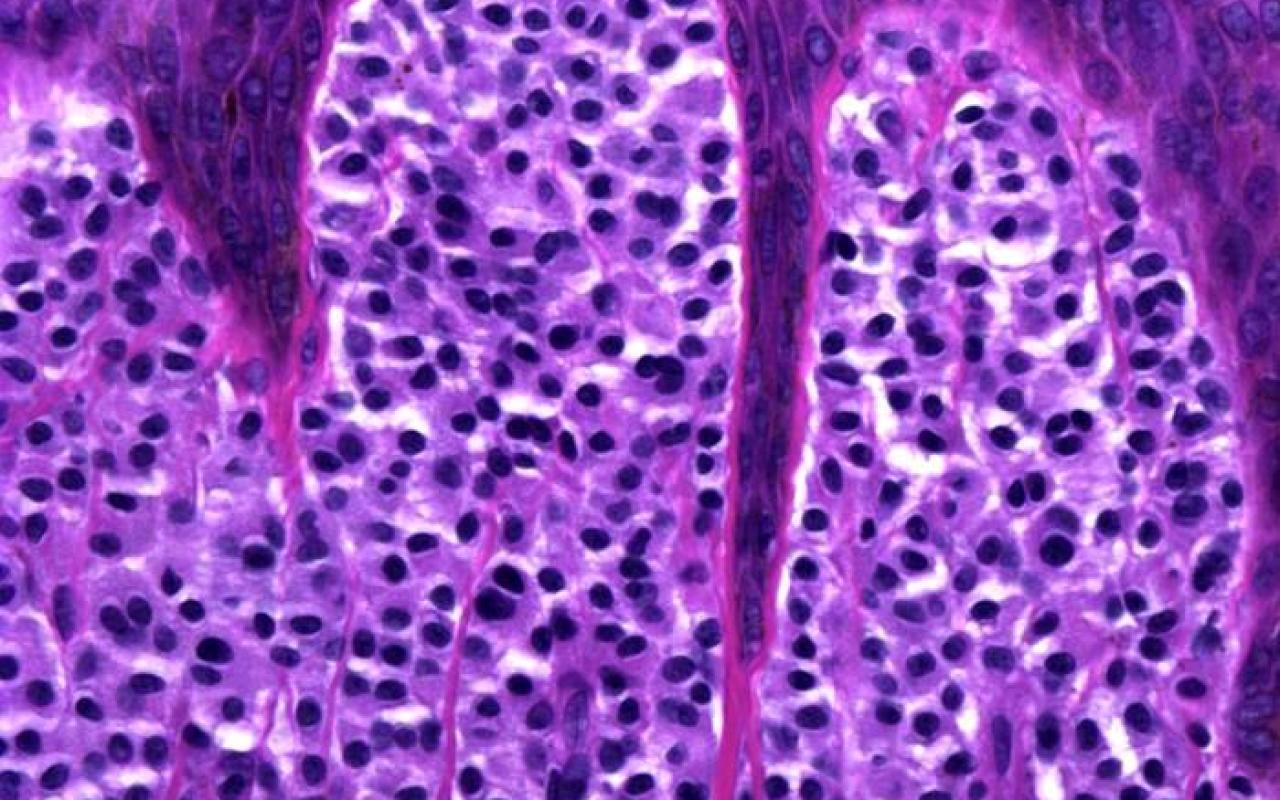

Correct choice:C. Metastatic adenocarcinoma

Explanation: In this image, the lymphatics are filled with large atypical cells trying to form glands making metastatic adenocarcionma the most likely diagnosis. Merkel cell carcinoma is a sheet of blue cells with salt and pepper nuclei. A lipoma is a collection of normal fat. Melanoma would have nests of atypical melanocytes. A myxoid neurothekeoma would be a loose collection of cells in thekes with a cellular stroma and the cells do not attempt to form glands.